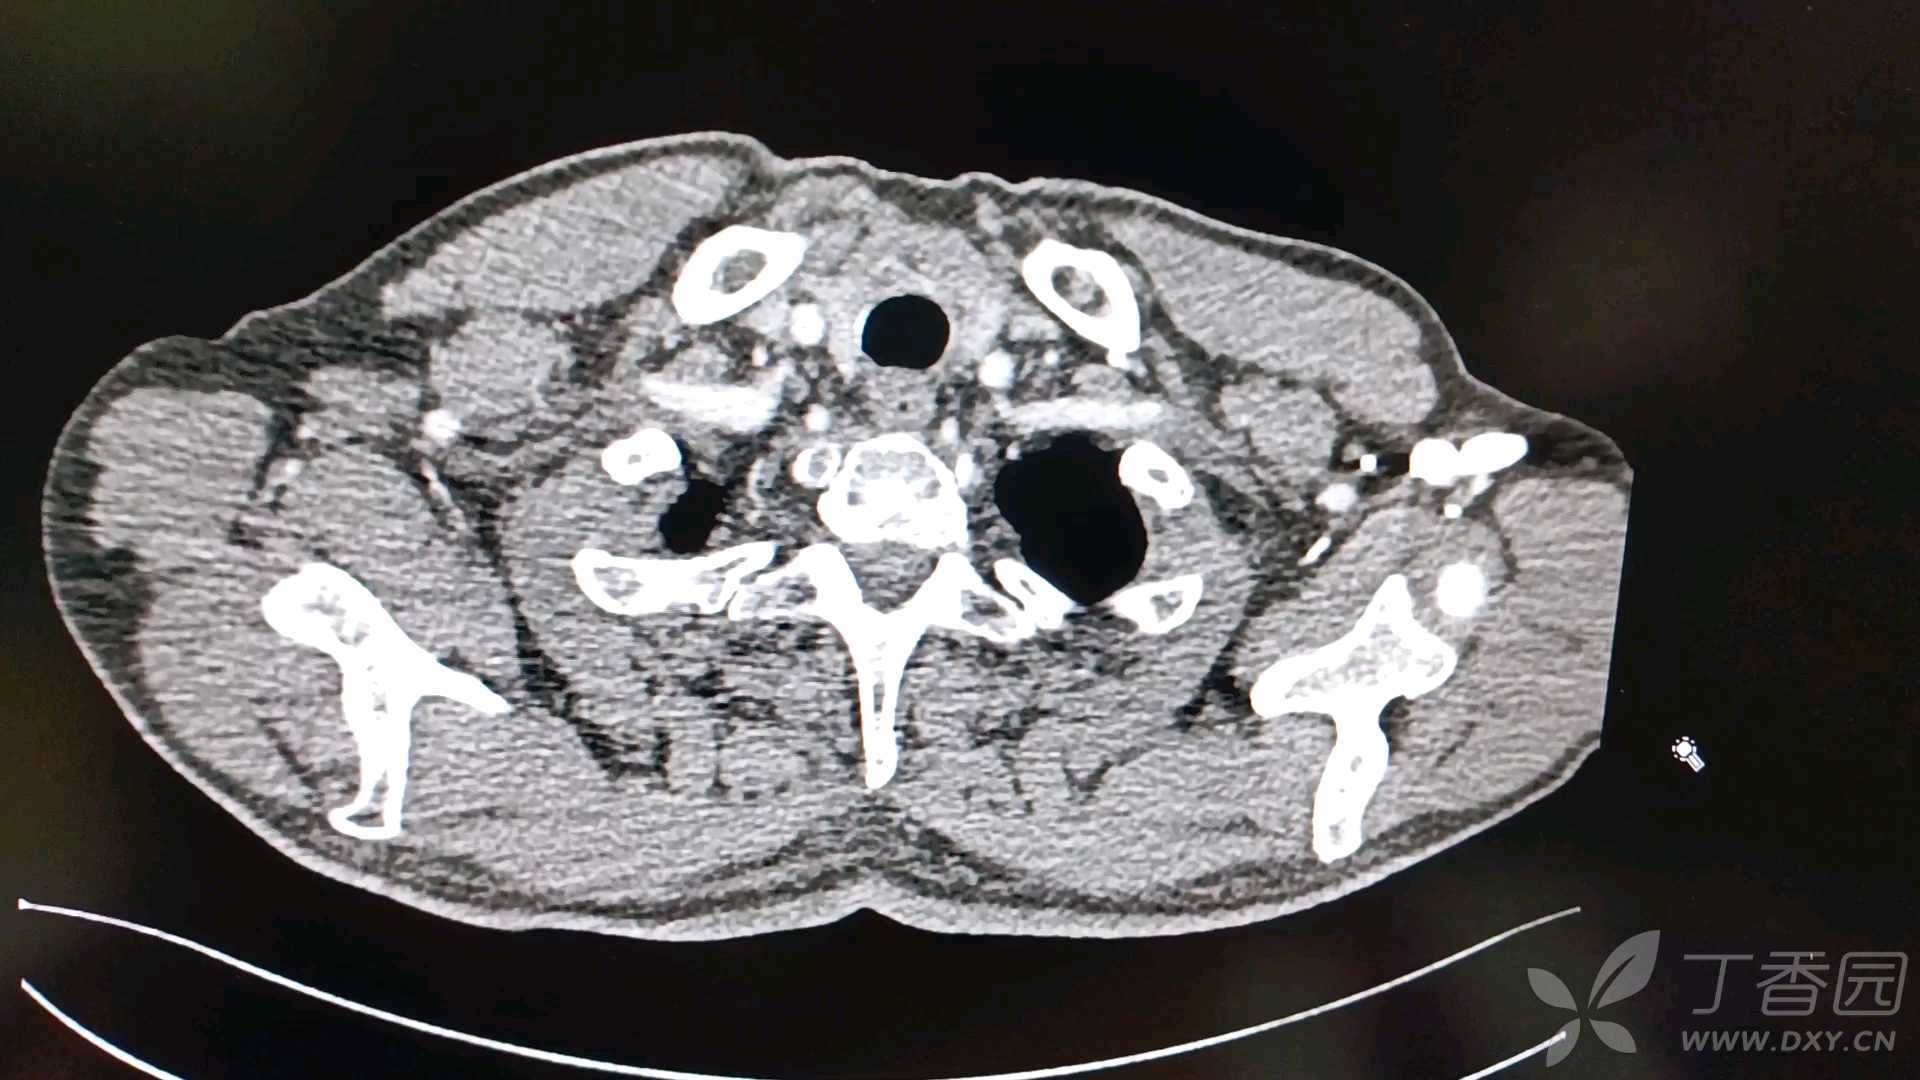

男性,68岁,查体发现肺占位5天。既往发现血糖增高4年余,甲亢病史20余年,曾口服碘治疗后复查甲功示甲减。